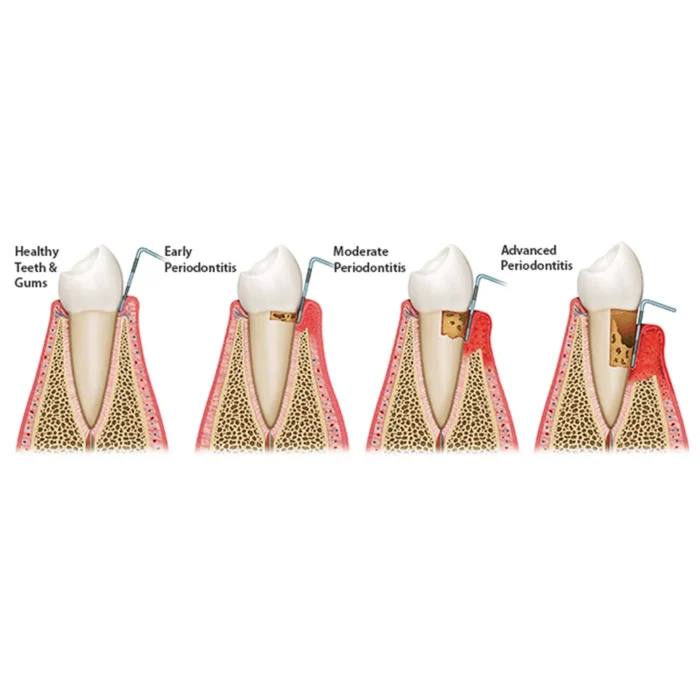

- Periodontal probing: The probe allows dentists and dental hygienists to assess the health of the gums and measure pocket depths. This information is crucial for diagnosing and monitoring gum disease or other oral health conditions.

GDC Double End Probes Unc 15 / Screening Probe #1 (PCP15/11.5) is a dental instrument used by dentists and dental hygienists for periodontal probing and screening. It consists of a double-ended design with different measurements on each end. The “Unc 15” marking refers to the first end of the probe.UNC15 Probe has markings mm1-2-3-4-5-6-7-8-9-10-11-12-13-14-15 and Screening Probe has markings mm 3.5-5.5-8.5-11.5 inscribed onto the head of these instruments for accuracy and readability.

The second end of the probe is labeled as “Screening Probe #1” or “PCP15/11.5.” This end is specifically designed for periodontal screening and measuring pocket depths. “PCP” stands for “Periodontal Community Probe,” and the number “15” indicates the working end’s diameter, which is 1.5 millimeters. The “11.5” represents the marking increments on the probe, indicating the millimeter markings from the tip of the probe to its base. These markings help measure the depth of periodontal pockets, which can be an indicator of gum disease or other oral health conditions.